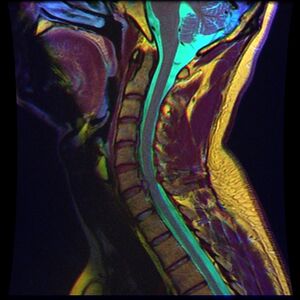

التصوير بالرنين المغناطيسي للانزلاق الغضروفي العنقي بين الفقرتين العنقيتين لخامسة والسادسة.

التصوير بالرنين المغناطيسي للانزلاق الغضروفي العنقي بين الفقرتين العنقيتين السادسة والسابعة.